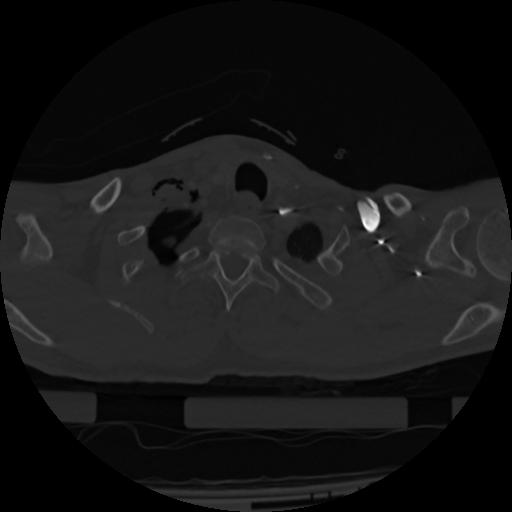

22 ANGIO,CE,Vol,0.5,ANGIO,,